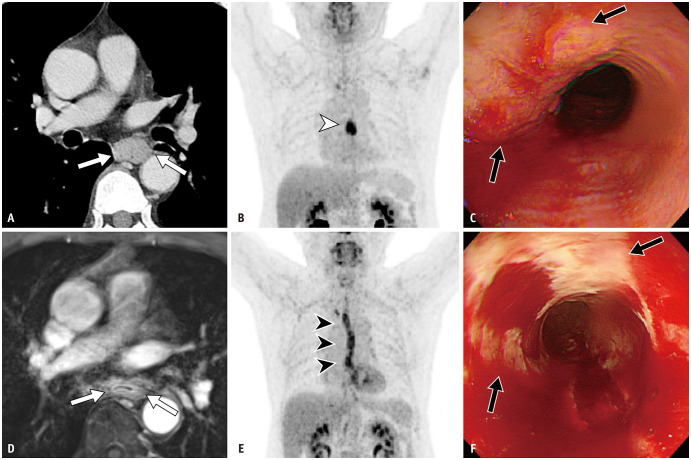

Materials and methods: Patients who underwent nCRT, subsequent MRI, positron emission tomography/computed tomography (PET/CT), endoscopy, or esophagectomy for esophageal cancer between October 2021 and October 2023 were retrospectively analyzed. The DCE-MRI response of primary tumors was interpreted using five grades by thoracic radiologists as follows: G1 (compatible with CR), G2 (probable CR), G3 (probable partial response [PR]), G4 (compatible with PR), and G5 (stable or progressive disease). The performances of MRI, PET/CT, endoscopy, and their combinations in diagnosing pCR in primary tumors were calculated.

Results: A total of 52 patients (male:female, 46:6; age, 61.2 ± 8.0 years) were included. Surgical specimens revealed pCR (ypT0) in 34 patients. G1 as the MRI criterion for pCR of primary tumors yielded a positive predictive value (PPV), specificity of 100% (18/18), and low sensitivity (23.5% [8/34]). Combining G1 and G2 as the MRI criteria increased the sensitivity to 73.5% (25/34), with a specificity of 88.9% (16/18), accuracy of 78.8% (41/52), and PPV of 92.6% (25/27). Adding the DCE-MRI results (G1-2) significantly improved accuracy for both PET/CT (from 65.4% [34/52] to 80.8% [42/52], P = 0.03) and endoscopy (from 55.8% [29/52] to 76.9% [40/52], P = 0.005), with increase in sensitivity (from 55.9% [19/34] to 82.4% [28/34] for PET/CT-based evaluation [P = 0.008] and from 47.1% [16/34] to 82.4% [28/34] for endoscopy-based evaluation [P = 0.001]).

Conclusion: DCE-MRI-based grading shows high diagnostic performance for identifying pCR in primary tumors, particularly in terms of PPV and specificity, and enhances response evaluation when combined with PET/CT and endoscopy.